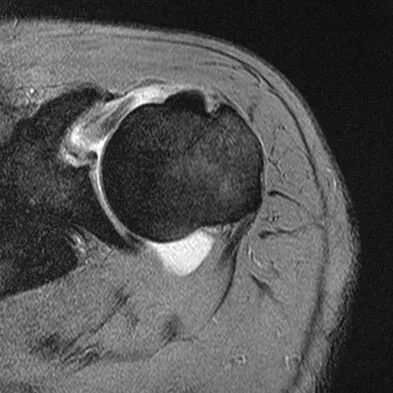

Figures 36a and 36b show the MRI scans of a patient who has shoulder weakness. What is the most likely diagnosis?

Explanation